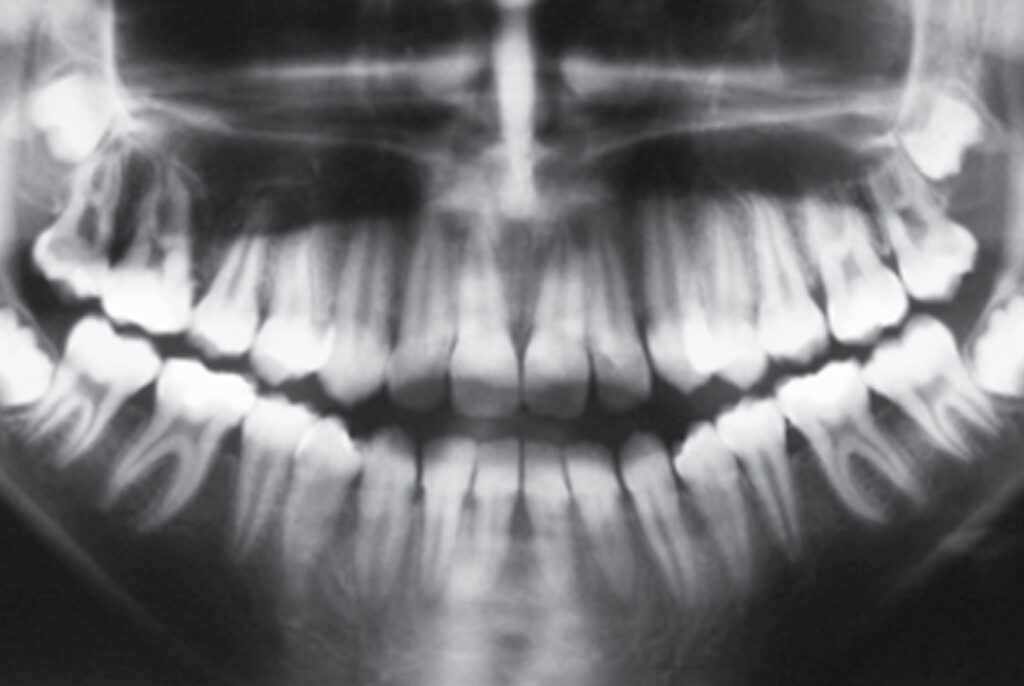

Na radiografia panorâmica, pode-se perceber a presença de todos os dentes, inclusive dos germes dos terceiros molares (Figura 3).